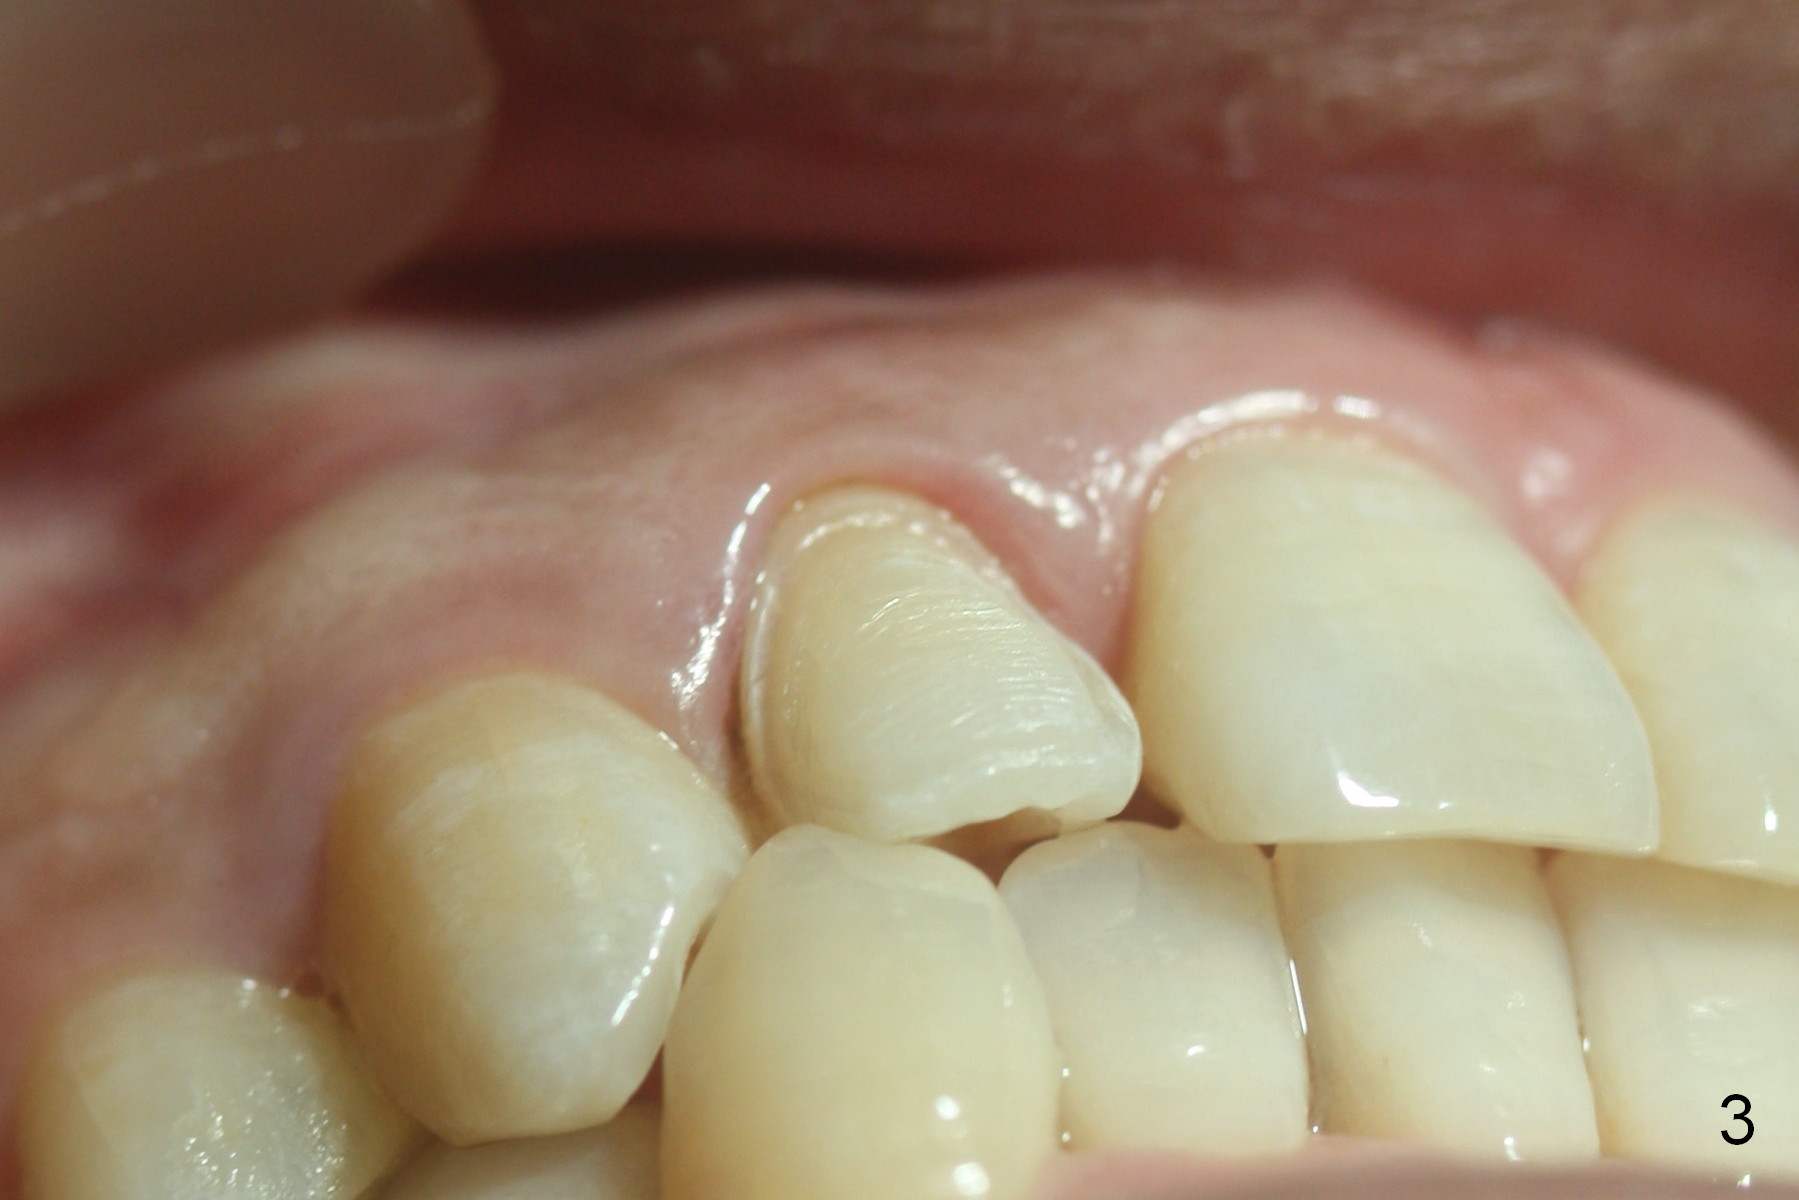

| Middle |

A 36-year-old man has 2 small, congenitally deformed lateral incisors (peg laterals, Fig.1,2 *). After discussion, we choose porcelain veneers for cosmetic makeup. The teeth need minor shaving (Fig.3,4); right colors are being selected with a shade guide (Fig.4: G). The shaving is so conservative that there is no pain during the procedure and there is no need to make temporary veneers. One to 2 weeks later, porcelain veneers are cemented (Fig.5,6). The patient is satisfied.